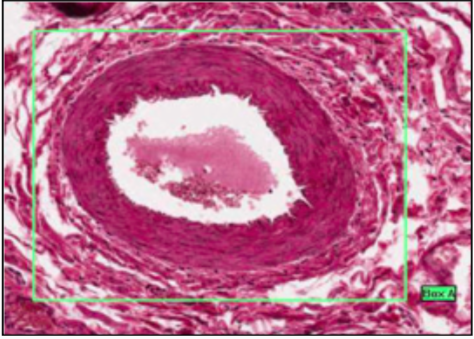

MUSCULAR ARTERY

- well defined medial layer (smooth muscle in concentric rings)

- medial layer interspersed with elastic

- media-intima divide = wavy internal elastic lamina (condensed perforated elastic)

- adventitia-media divie = external elastic lamina only in large muscular